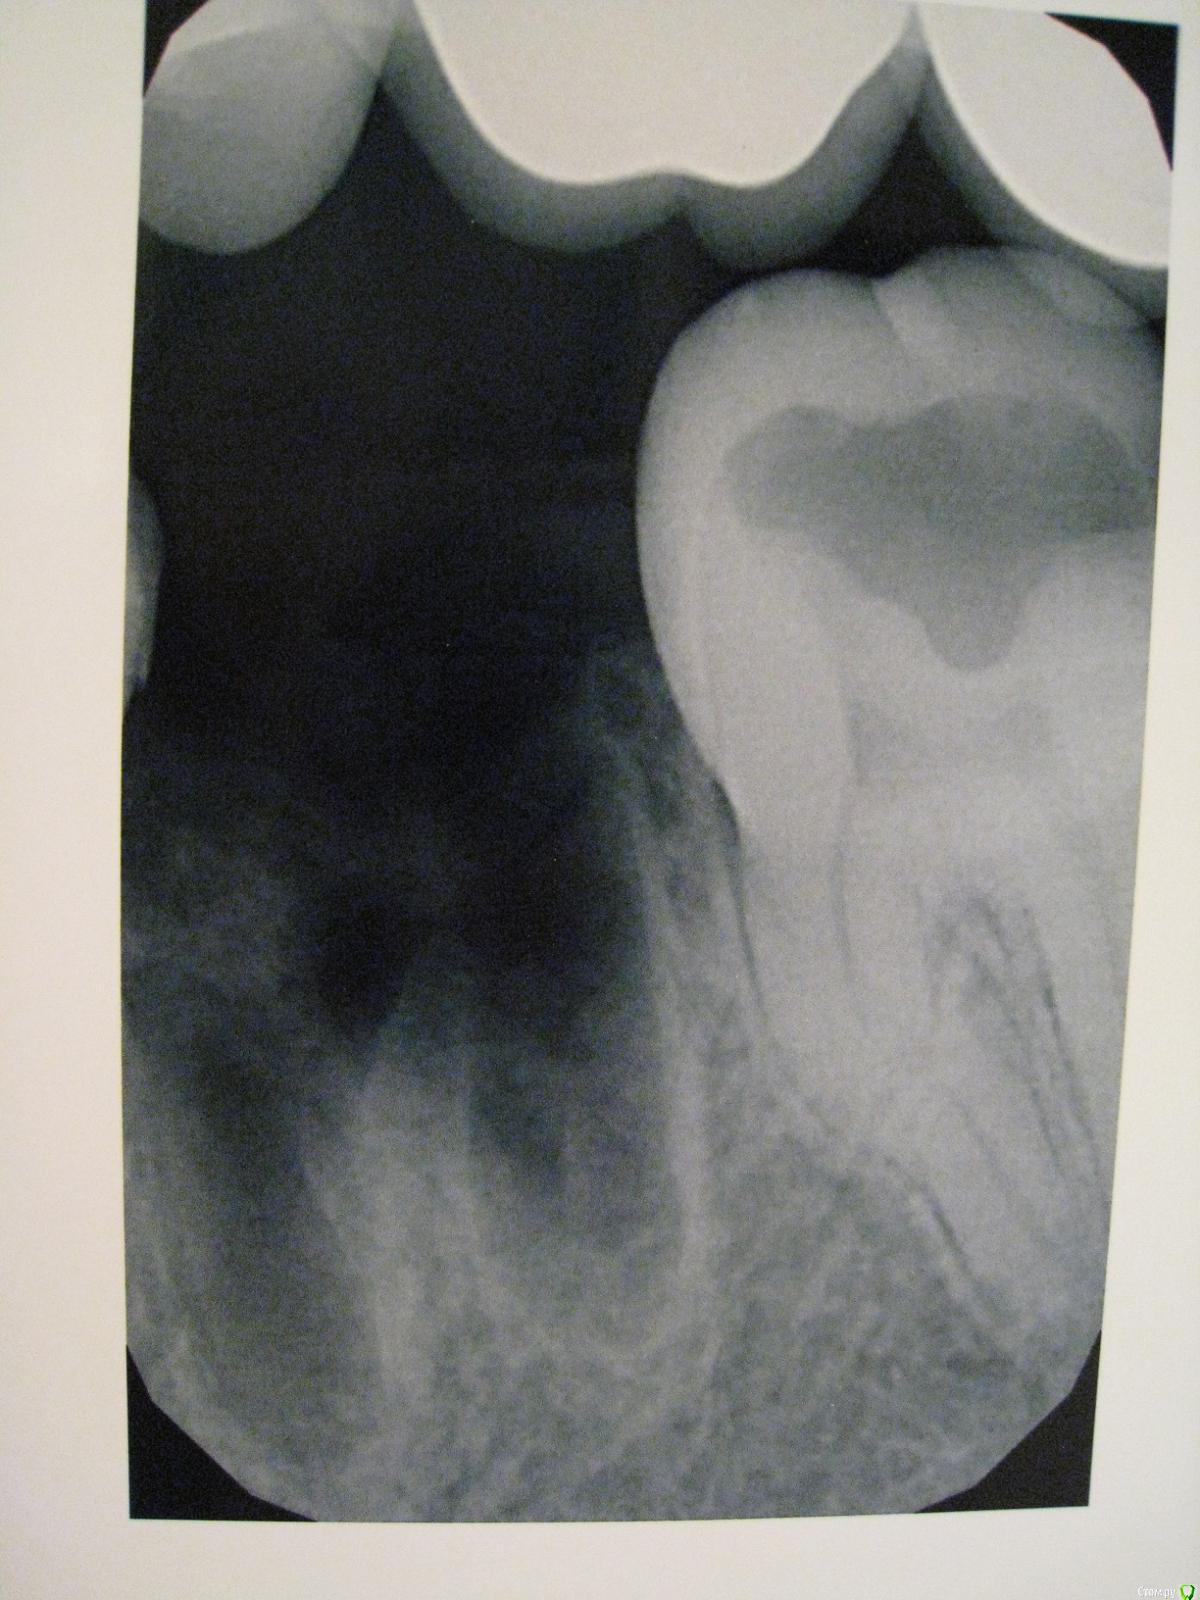

АнтонТЛТ Опубликовано 16 декабря, 2016 Поделиться Опубликовано 16 декабря, 2016 Осколка зуба на снимке нет 4 Ссылка на комментарий

red_butler Опубликовано 19 декабря, 2016 Поделиться Опубликовано 19 декабря, 2016 Фото сделать сложно, но примерно вот такие у меня насечки на десне. без фото на вопрос не ответить. По Rg зуб удален полностью и аккуратно. 1 1 Ссылка на комментарий